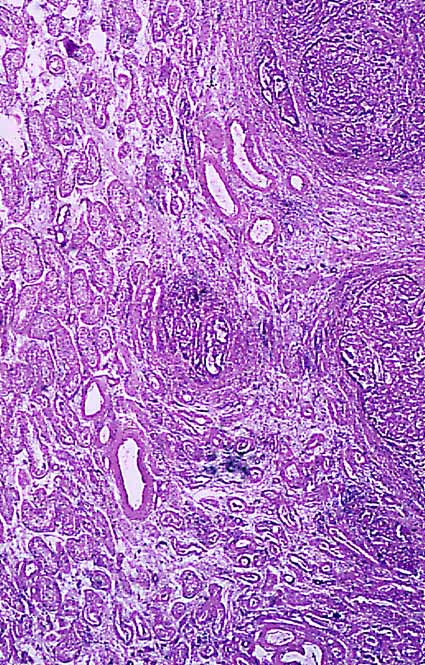

fig. 2

Figura 2.- Adenocarcinoma (H&E X 40): Pequeño islote tumoral en el centro y túbulos seminíferos normales alrededor.